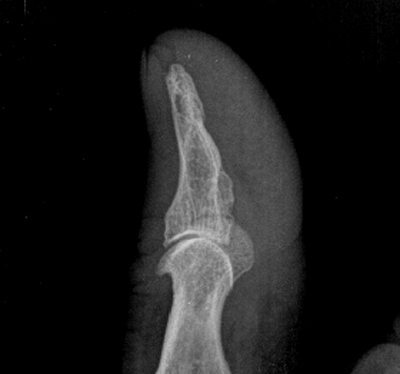

标题: X3013:男70岁,半年前拇指砸伤,近日拇指日夜疼痛。 [打印本页]

标题: X3013:男70岁,半年前拇指砸伤,近日拇指日夜疼痛。

男70岁,半年前拇指砸伤,近日拇指日夜疼痛。

植入性骨囊肿又称外伤性上皮植入性骨囊肿与创伤有关,病变多发生在末节指骨,病人都有数年以上的外伤史,手指软组织砸伤后,使小片上皮断离,并埋藏于皮下,而后逐渐移植于骨组织内,长时间增殖,生长,形成上皮样骨囊肿。

x线检查,动脉瘤样骨囊肿表现为干骺端偏心性的低密性病损。骨膜抬高、隆起、皮质往往被侵蚀至菲薄外壳。有皂泡样(soap bubble)和爆裂样(blow out)表现。ct扫描对骨盆,脊柱病变有较高的临床价值,ct扫描能很好显示腔内的多灶性的液平,所以对鉴别单纯性骨囊肿意义较大,mri检查同样能显示多灶液平,并能判断腔内液是否为血性。动脉瘤样骨囊肿mri的t1、t2相表现均为低信号边缘包绕囊性缺损。如果怀疑,一定注意仔细观片以发现可能存在的前原发病种的特征表现。有个别动脉瘤样骨囊肿可有絮状软骨基质成份表现,这可以用以判断其病理发生学的来源。

结合本例外伤史及征象,考虑上皮植入性囊肿可能性大。